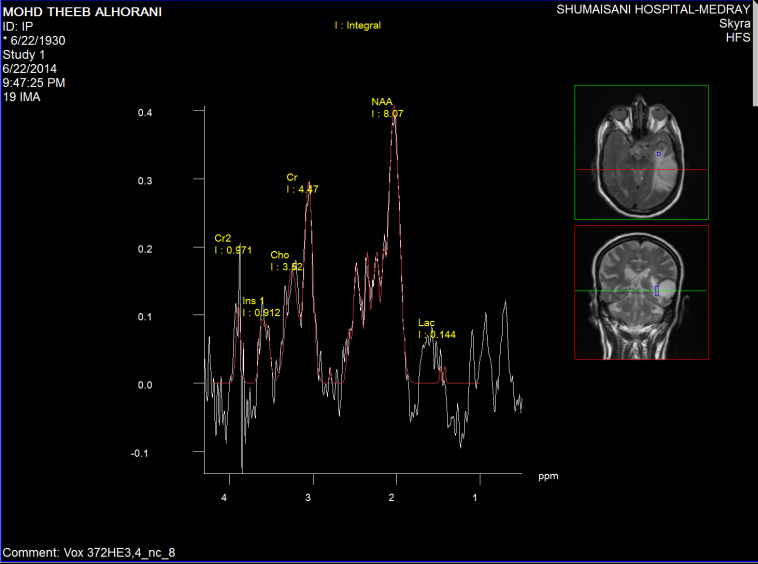

Spectroscopy was done the day before surgery, supporting data for MTS (Figure1-6).

Figure-2: Short TE spectroscopy showing low Choline and high Cr and NAA with low LIP 13 and 09  and low lactate, ruling out the presence of malignant cloud around the tumor.